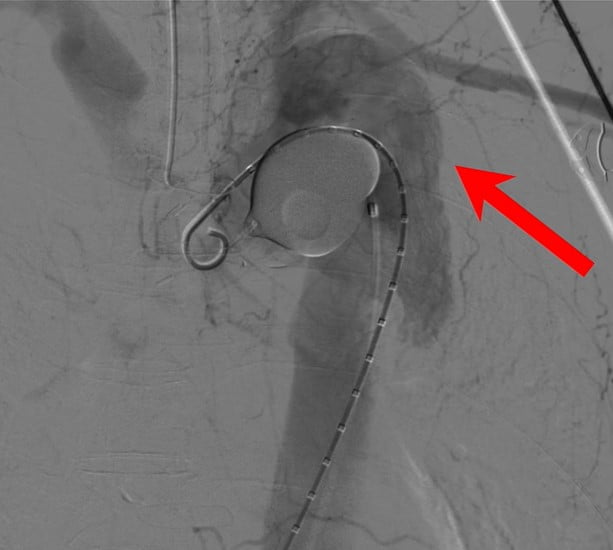

Aortic Stent Graft